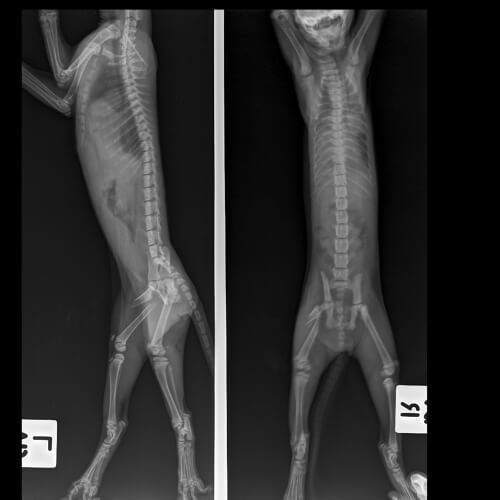

Gatos cojos y procedimientos diagnósticos

Es necesario resaltar la importancia de obtener el diagnóstico correcto para que el gato no desarrolle trastornos musculares o nerviosos permanentes. Tu veterinario realizará un examen físico completo de tu gato para ayudar a determinar la ubicación exacta del problema.

La edad de su gato, el historial de cualquier trauma, el inicio del problema (agudo o crónico), la gravedad de la cojera, y si hay múltiples patas involucradas, son indicadores de la posible fuente del problema.

El diagnóstico de gatos cojos puede requerir pruebas especiales. Es frecuente que incluya uno o más de los siguientes análisis:

- Radiografías.